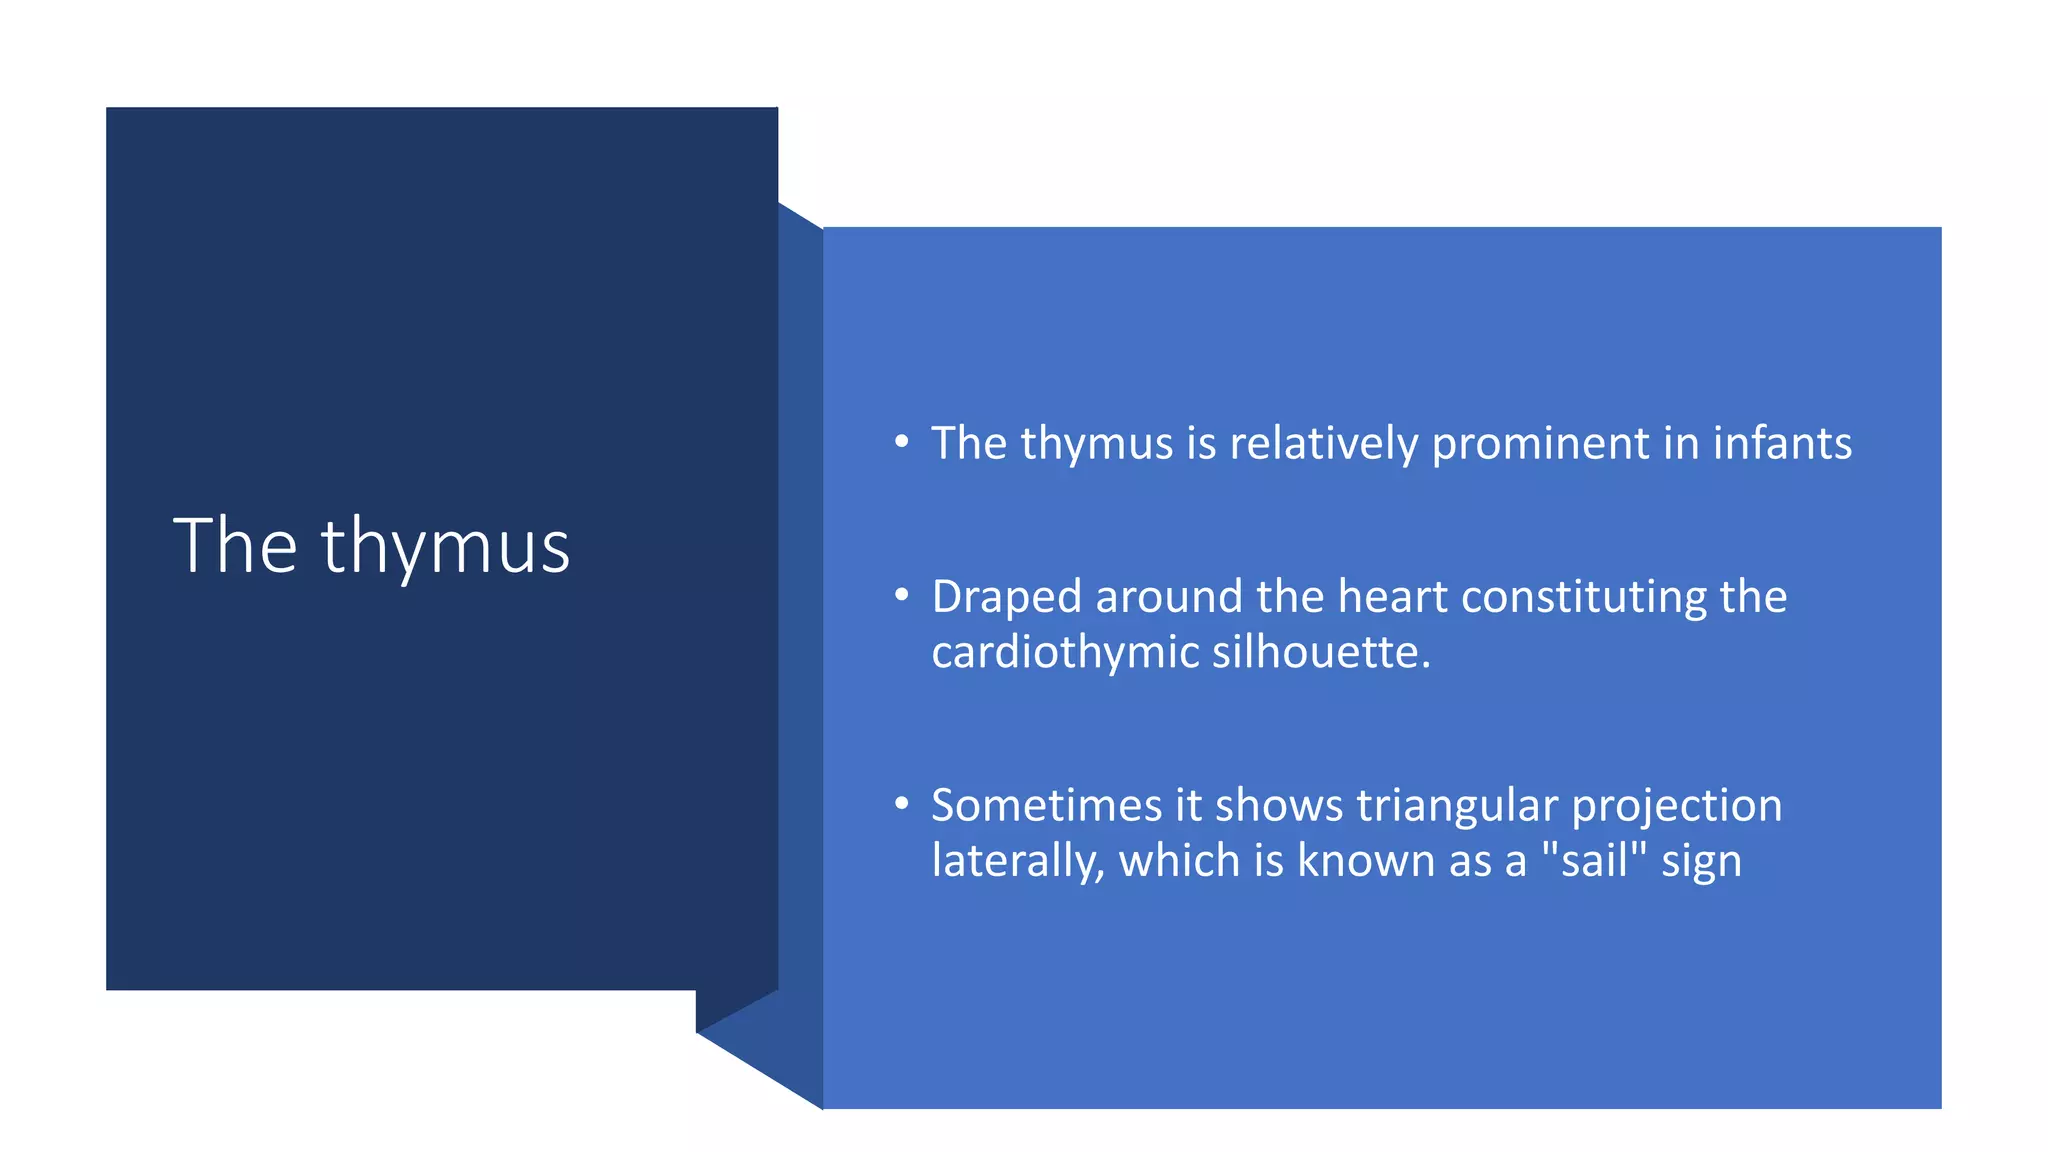

This document provides an overview of neonatal chest x-rays, including when they should and should not be performed, what a normal x-ray looks like, common positions of tubes and catheters, and common causes of respiratory distress in neonates. It discusses the appearance of a normal chest x-ray as well as conditions like respiratory distress syndrome, transient tachypnea of the newborn, meconium aspiration syndrome, and pneumonia. Surgical conditions like diaphragmatic hernia and esophageal atresia are also reviewed.